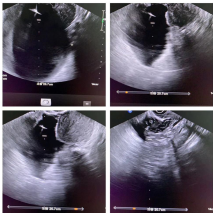

日前,某位腹部不适患者来到我院超声二科就医,值班大夫给患者进行常规检查,惊讶地发现其下腹部有一大小约20×20×10cm巨大囊肿,壁光滑,透声好,大略估测囊液量约2000ml(4斤重),囊壁及周边均未发现明显其他异常超声征象。经综合判断并依据患者主观意愿,医患双方决定选择行操作简便、费用低、创伤小的“阴式超声引导下盆腔囊性肿物穿刺术”来解决这个棘手问题。

经过术前常规会阴部消毒,在阴式超声引导下,李继光主任及杨黎主任联手配合,一根20cm18G细针巧妙地避开了血管及腹部脏器准确刺入囊肿内,经20分钟左右抽吸操作,共抽出2100ml清亮囊液。因操作无须麻醉,患者与操作医护们在术中一同见到了囊肿由大变小、直至消失的过程,整个过程患者没有感到疼痛等不适。只是“扎了一针”,4斤重的巨大囊肿就消失了,腹部不适症状也随之消除了,而且治疗时间之短、费用之低、效果之理想,完全超出了患者及家人的想象。手术结束后密切观察30分钟无特殊情况,患者满意地自己走出了诊室,且不需要留院观察。术后抽取液被送至病理科进行相关检查,杨鹏医师回报未发现肿瘤细胞,至此整个治疗过程圆满结束。